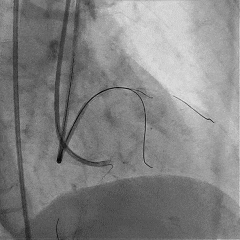

于LAD近中段植入Tivoli 2.75*33mm支架一枚,高压球囊后扩张后,血流TIMI3级

Sion导丝至LCX远端,预扩球囊扩张后,植入支架XIENCEAlpine 2.25*23mm支架一枚

术后造影支架膨胀良好,血流TIMI3级